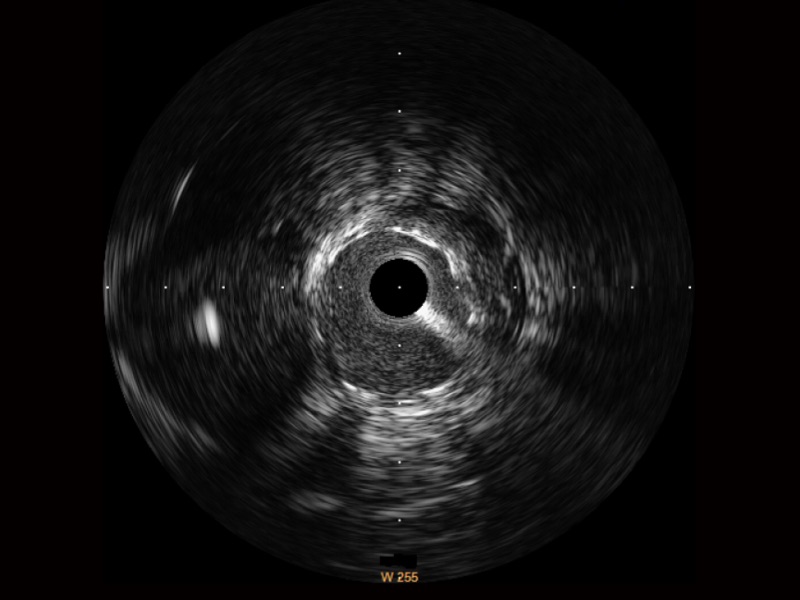

• 不朽情缘宽频IVUS图像

对比传统IVUS导管成像,不朽情缘宽频IVUS图像的近场支架梁显影更细腻,远场中膜外血管仍清晰可辨,兼顾远中近,兼顾分辨力与穿透深度